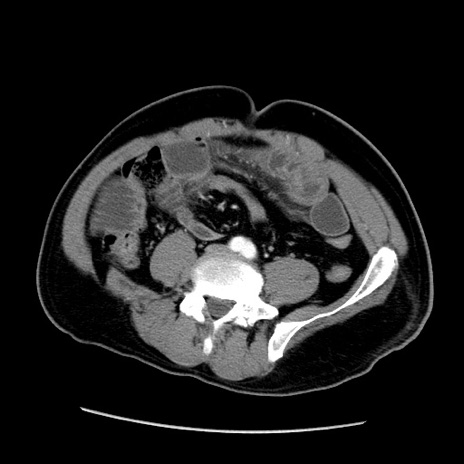

症例22(横断像)

【症例】50歳代男性

【主訴】腹痛

【現病歴】AVMからの被殻出血のため回復期リハ病棟入院中。 本日午後3時頃急に下腹部痛が出現した。

【既往歴】AVM、被殻出血、虫垂炎、高血圧

【身体所見】意識晴明、左半身不全麻痺、会話の理解は良好、36.5°C、腹部:膨隆、全体に板状硬、下腹部正中に圧痛点あり、反跳痛-、筋性防御不明、右下腹部にope scar

【データ】WBC 9400、CRP 0.06